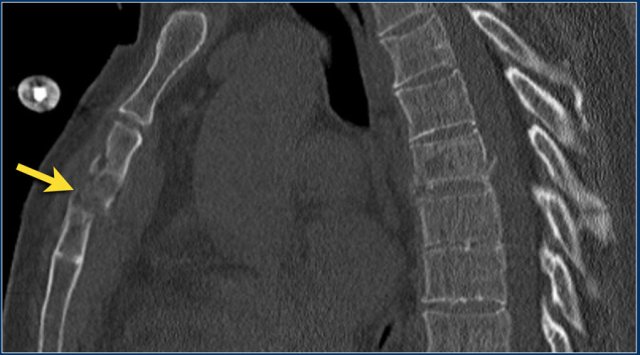

The images are of a patient with a typical bamboo spine as a result of ankylosing spondylitis.

After a fall on his back no fracture was seen on the x-rays.

However the CT shows a thin fracture line through the anterior side of the vertebral body and also through the spinous process.

Continue with the MR-images.

The findings are:

1. Vertebral bodies show marrow edema as a result of a fracture.

2. Torn flaval ligament (yellow arrow).

3. Fractures through the posterior elements (red arrows).

The TLICS-score is high, because there is distraction and injury to the PLC.